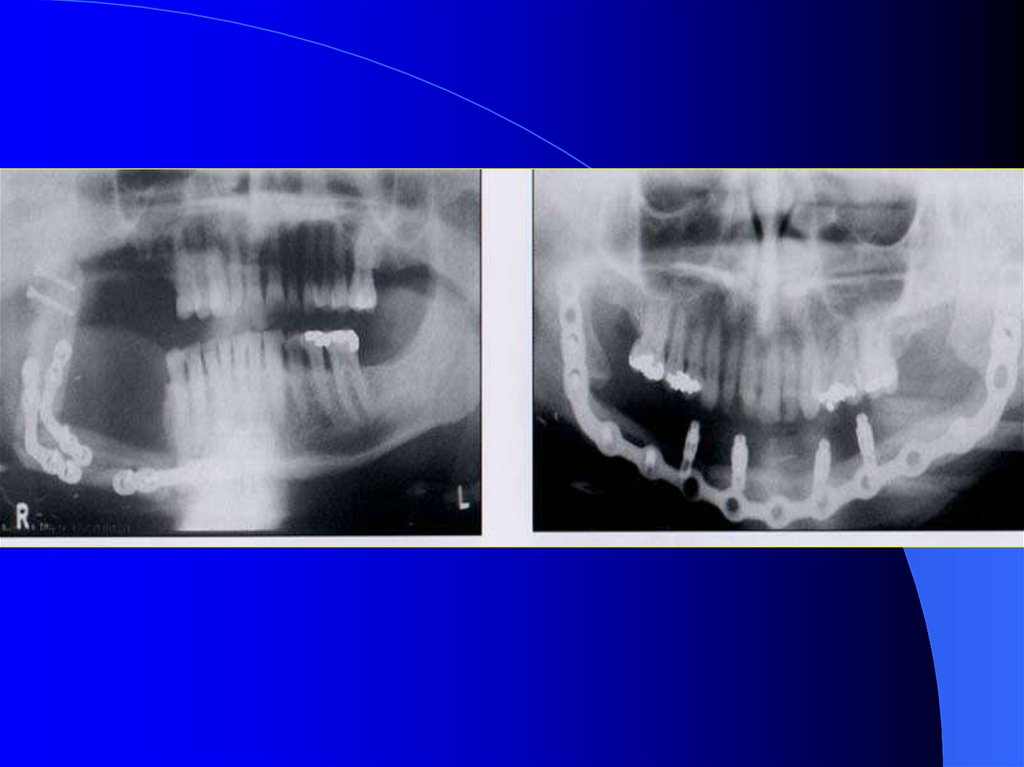

31. Alt çene devamlılığı olmayan dişsiz hastalar

Tedavisi en zor olan vakalardır. Klinikte

sıklıkla rastlanmaktadır.

Dil, yanaklar, çevre dokular protezin cilalı

yüzeyleriyle ve dişleri ile uyum sağladığı

ölçüde stabilte artar.

Skatris dokuları ve cerrahi işlem yapılan

bölgedeki hissizlik protezi olumsuz etkiler.

32. Devamlılığın bozulduğu durumlarda oklüzyonun sağlanması:

1- El kontrolü ile yapılan egzersizlerle

kapanış ilişkisinin sağlanması

2-Rehber düzlemler hazırlanması

3-Azılar bölgesinde çift sıra diş dizimi

4-Azılar bölgesinde palatinalde rehber

akrilik düzlemler hazırlanması